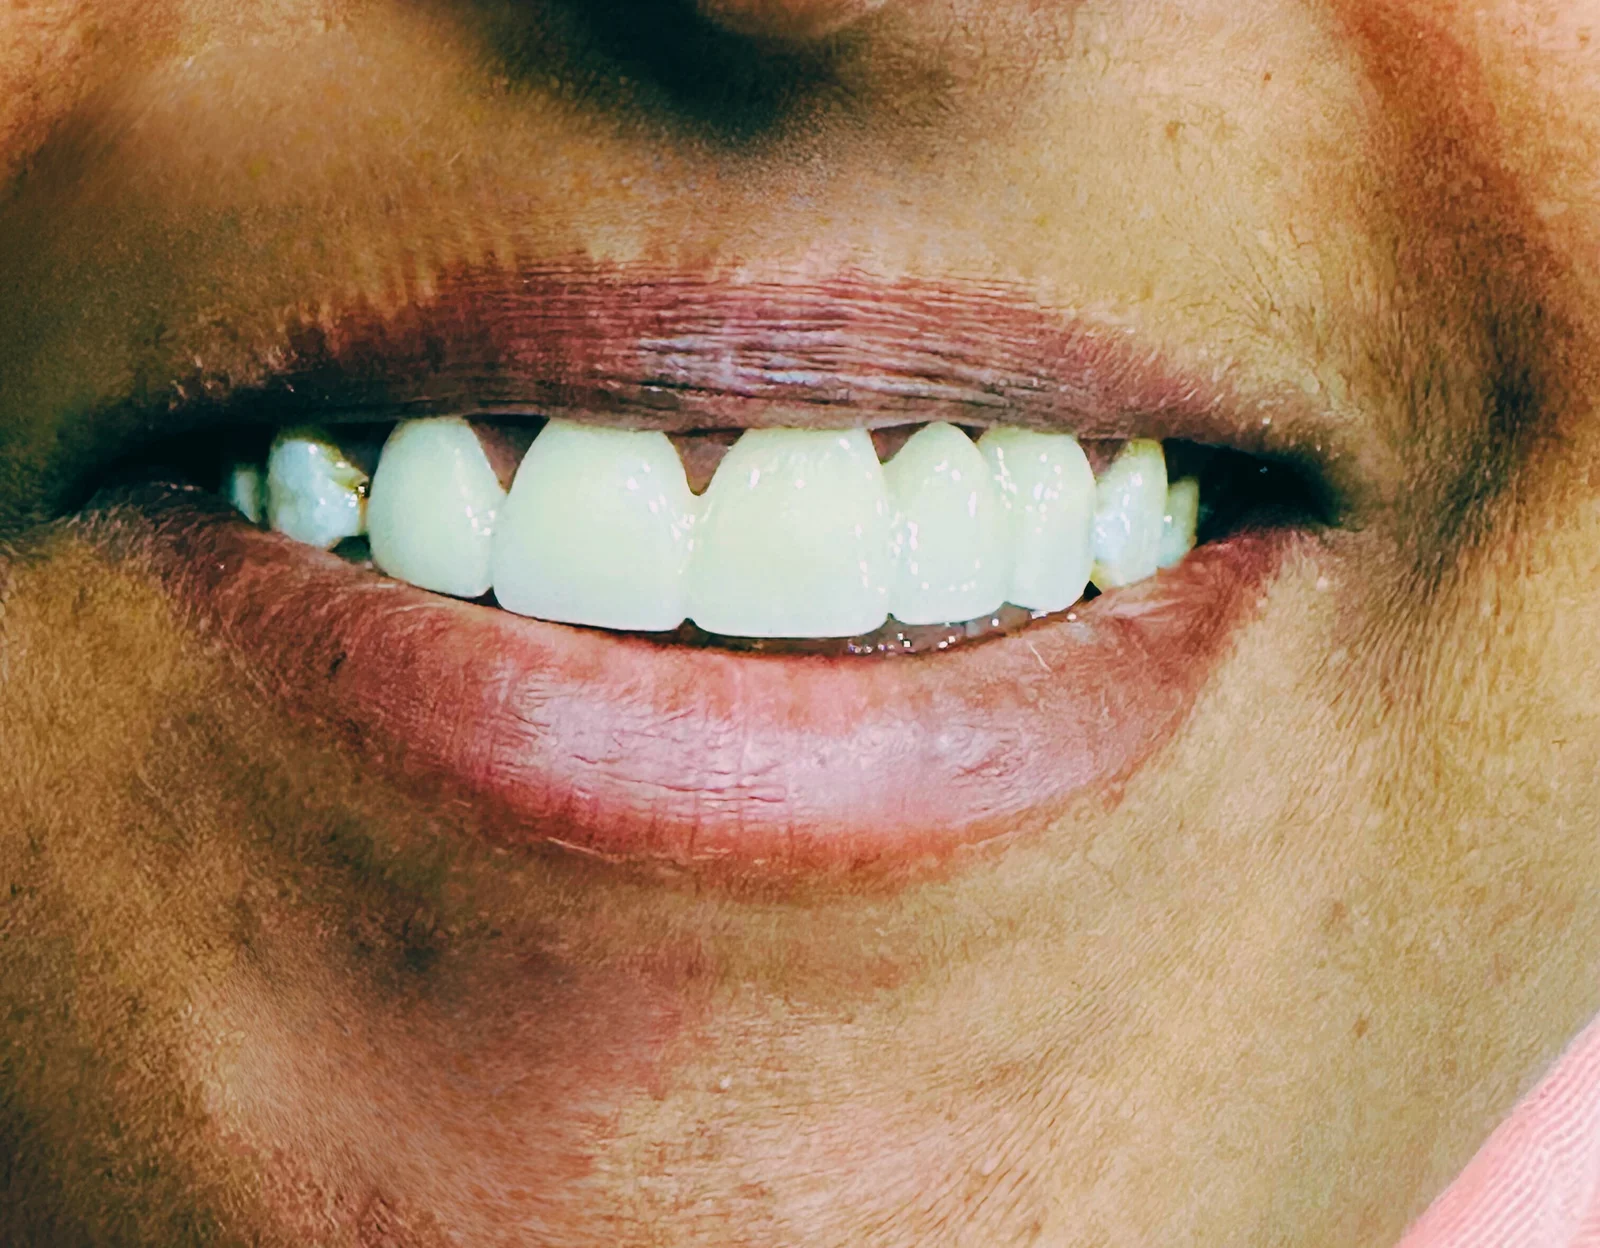

23 Jul 2025Complaint

Increasing gap between front teeth

Missing lateral incisor

Yellowish fluoride stains

Forwardly placed (protruding) upper front teeth

Discoloration due to fluorosis

Spacing and midline diastema

Missing lateral tooth

Esthetic concern with anterior crowding and projection

Root canal treatment of 4 upper front teeth

Smile correction using a 5-unit zirconia bridge

Patient personally selected the final shade

A dramatic aesthetic improvement

Gaps closed

Alignment corrected

Shade matched to her satisfaction

Result: Patient reported zero pain throughout the procedure,She was extremely happy with the transformation